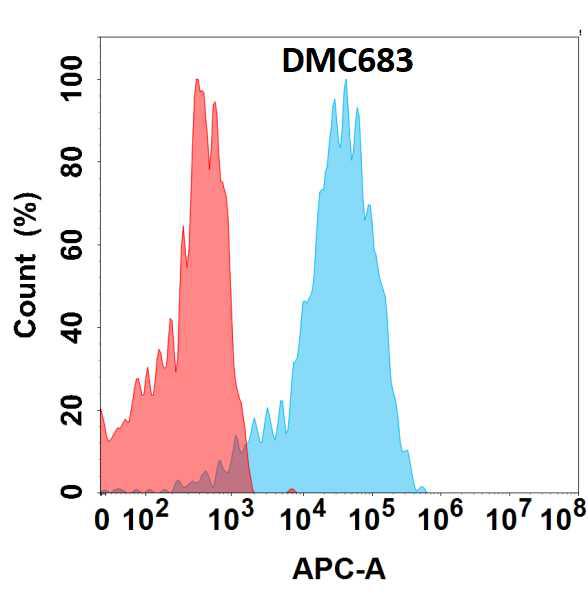

Anti-p21WAF1 (Tumor Suppressor Protein) Recombinant Rabbit Monoclonal Antibody (Clone:CIP1/2275R)

Figure 1: Formalin-fixed, paraffin-embedded human Urothelial Carcinoma stained with p21 Rabbit Recombinant Monoclonal Antibody (CIP1/2275R).

This MAb recognizes a 21kDa protein, identified as the p21WAF1 tumor suppressor protein. This MAb is highly specific to p21 and shows no cross-reaction with other closely related mitotic inhibitors. p21WAF1 is a specific inhibitor of cdk s and a tumor suppressor involved in the pathogenesis of a variety of malignancies. The expression of this gene acts as an inhibitor of the cell cycle during G1 phase and is tightly controlled by the tumor suppressor protein p53. Its expression is induced by the wild type, but not mutant, p53 suppressor protein. Normal cells generally display a rather intense nuclear p21 expression. Loss of p21 expression has been reported in many carcinomas (gastric carcinoma, non-small cell lung carcinoma, thyroid carcinoma).

Western Blot (1-2µg/ml); Immunohistochemistry (Formalin-fixed) (1-2µg/ml for 30 minutes at RT)(Staining of formalin-fixed tissues requires heating tissue sections in 10mM Tris with 1mM EDTA, pH 9.0, for 45 min at 95°C followed by cooling at RT for 20 minutes);